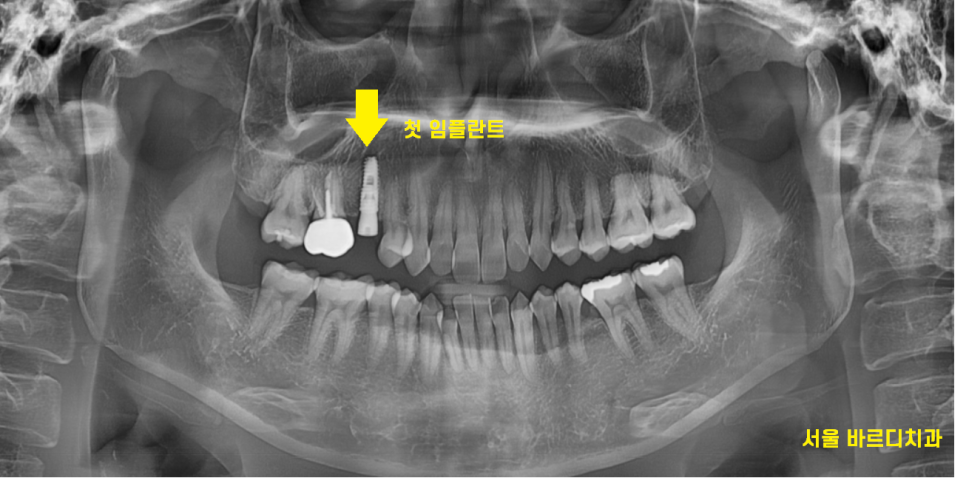

24.05.20

강동구 임플란트 1개 식립 완료한 사진입니다.

이 1개의 임플란트를 위해서

어떤 노력을 했을까요~?

임플란트 사이즈

뼈이식 과정, 느낌,결과

수술 후 안내해드려야하는 것

주의사항

당연히 진행해드렸고요.